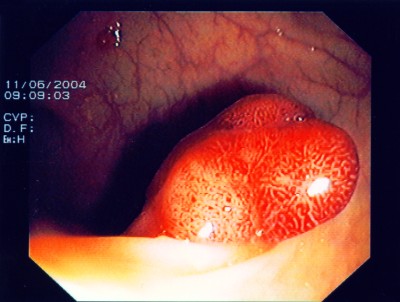

Großer Polyp des Dickdarmes

Wie bei den Abbildungen 28 und 30 handelt es sich um einen breitbasigen, relativ flachen, noch nicht entarteten Polyp, der sich mit einer Schlinge nicht vollständig abtragen ließe.